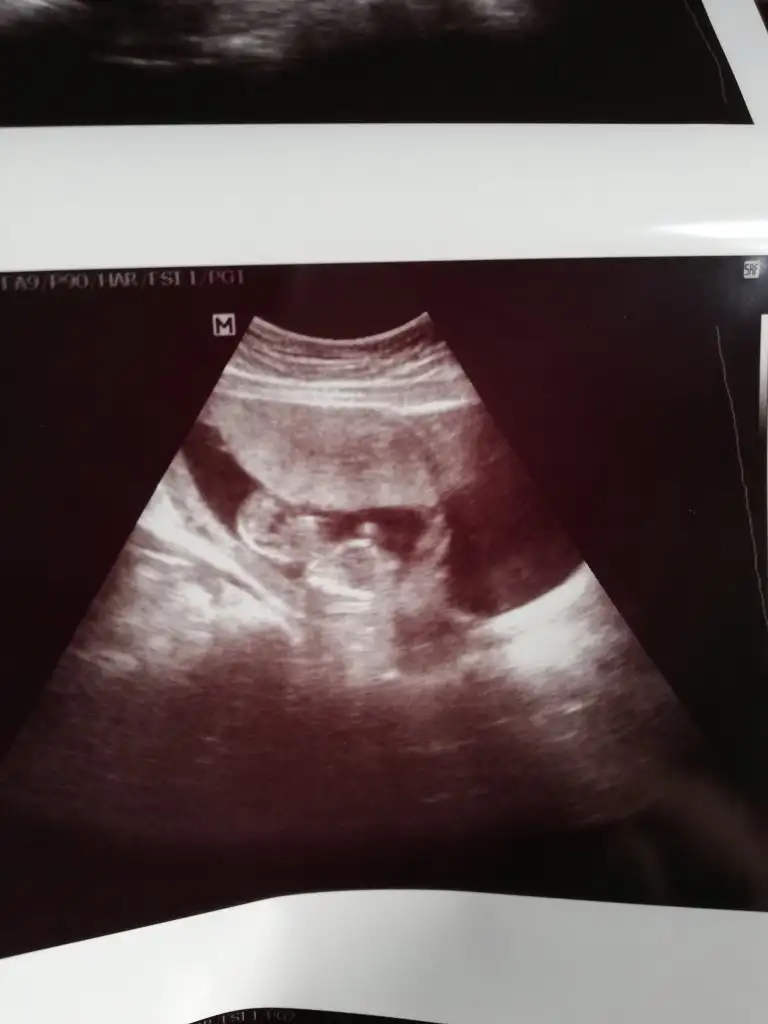

tmm ben ayrıntılı ultrasonda netleşince size dönüş yapacağımBencede kız 2 defa kız demiş aynı drusg de nub da kız gibi geri dönüş yaparsanız sevinirim

Sanki kız gibi eminde olamadım

Kız gibi gibi diyorum net değil usg başka varsa paylaşın emin olamadım12+4 günlük yorumlayabilir misiniz![]()

Sanki kız gibi ama emin değilim nubu karanlık kalmış 12 yada 13 haftada paylaşın emin olmak istiyorum![]()

Maalesef başka ultroson fotoğrafı yok. Kontrole gidersem atarım. TeşekkürlerKız gibi gibi diyorum net değil usg başka varsa paylaşın emin olamadım![]()